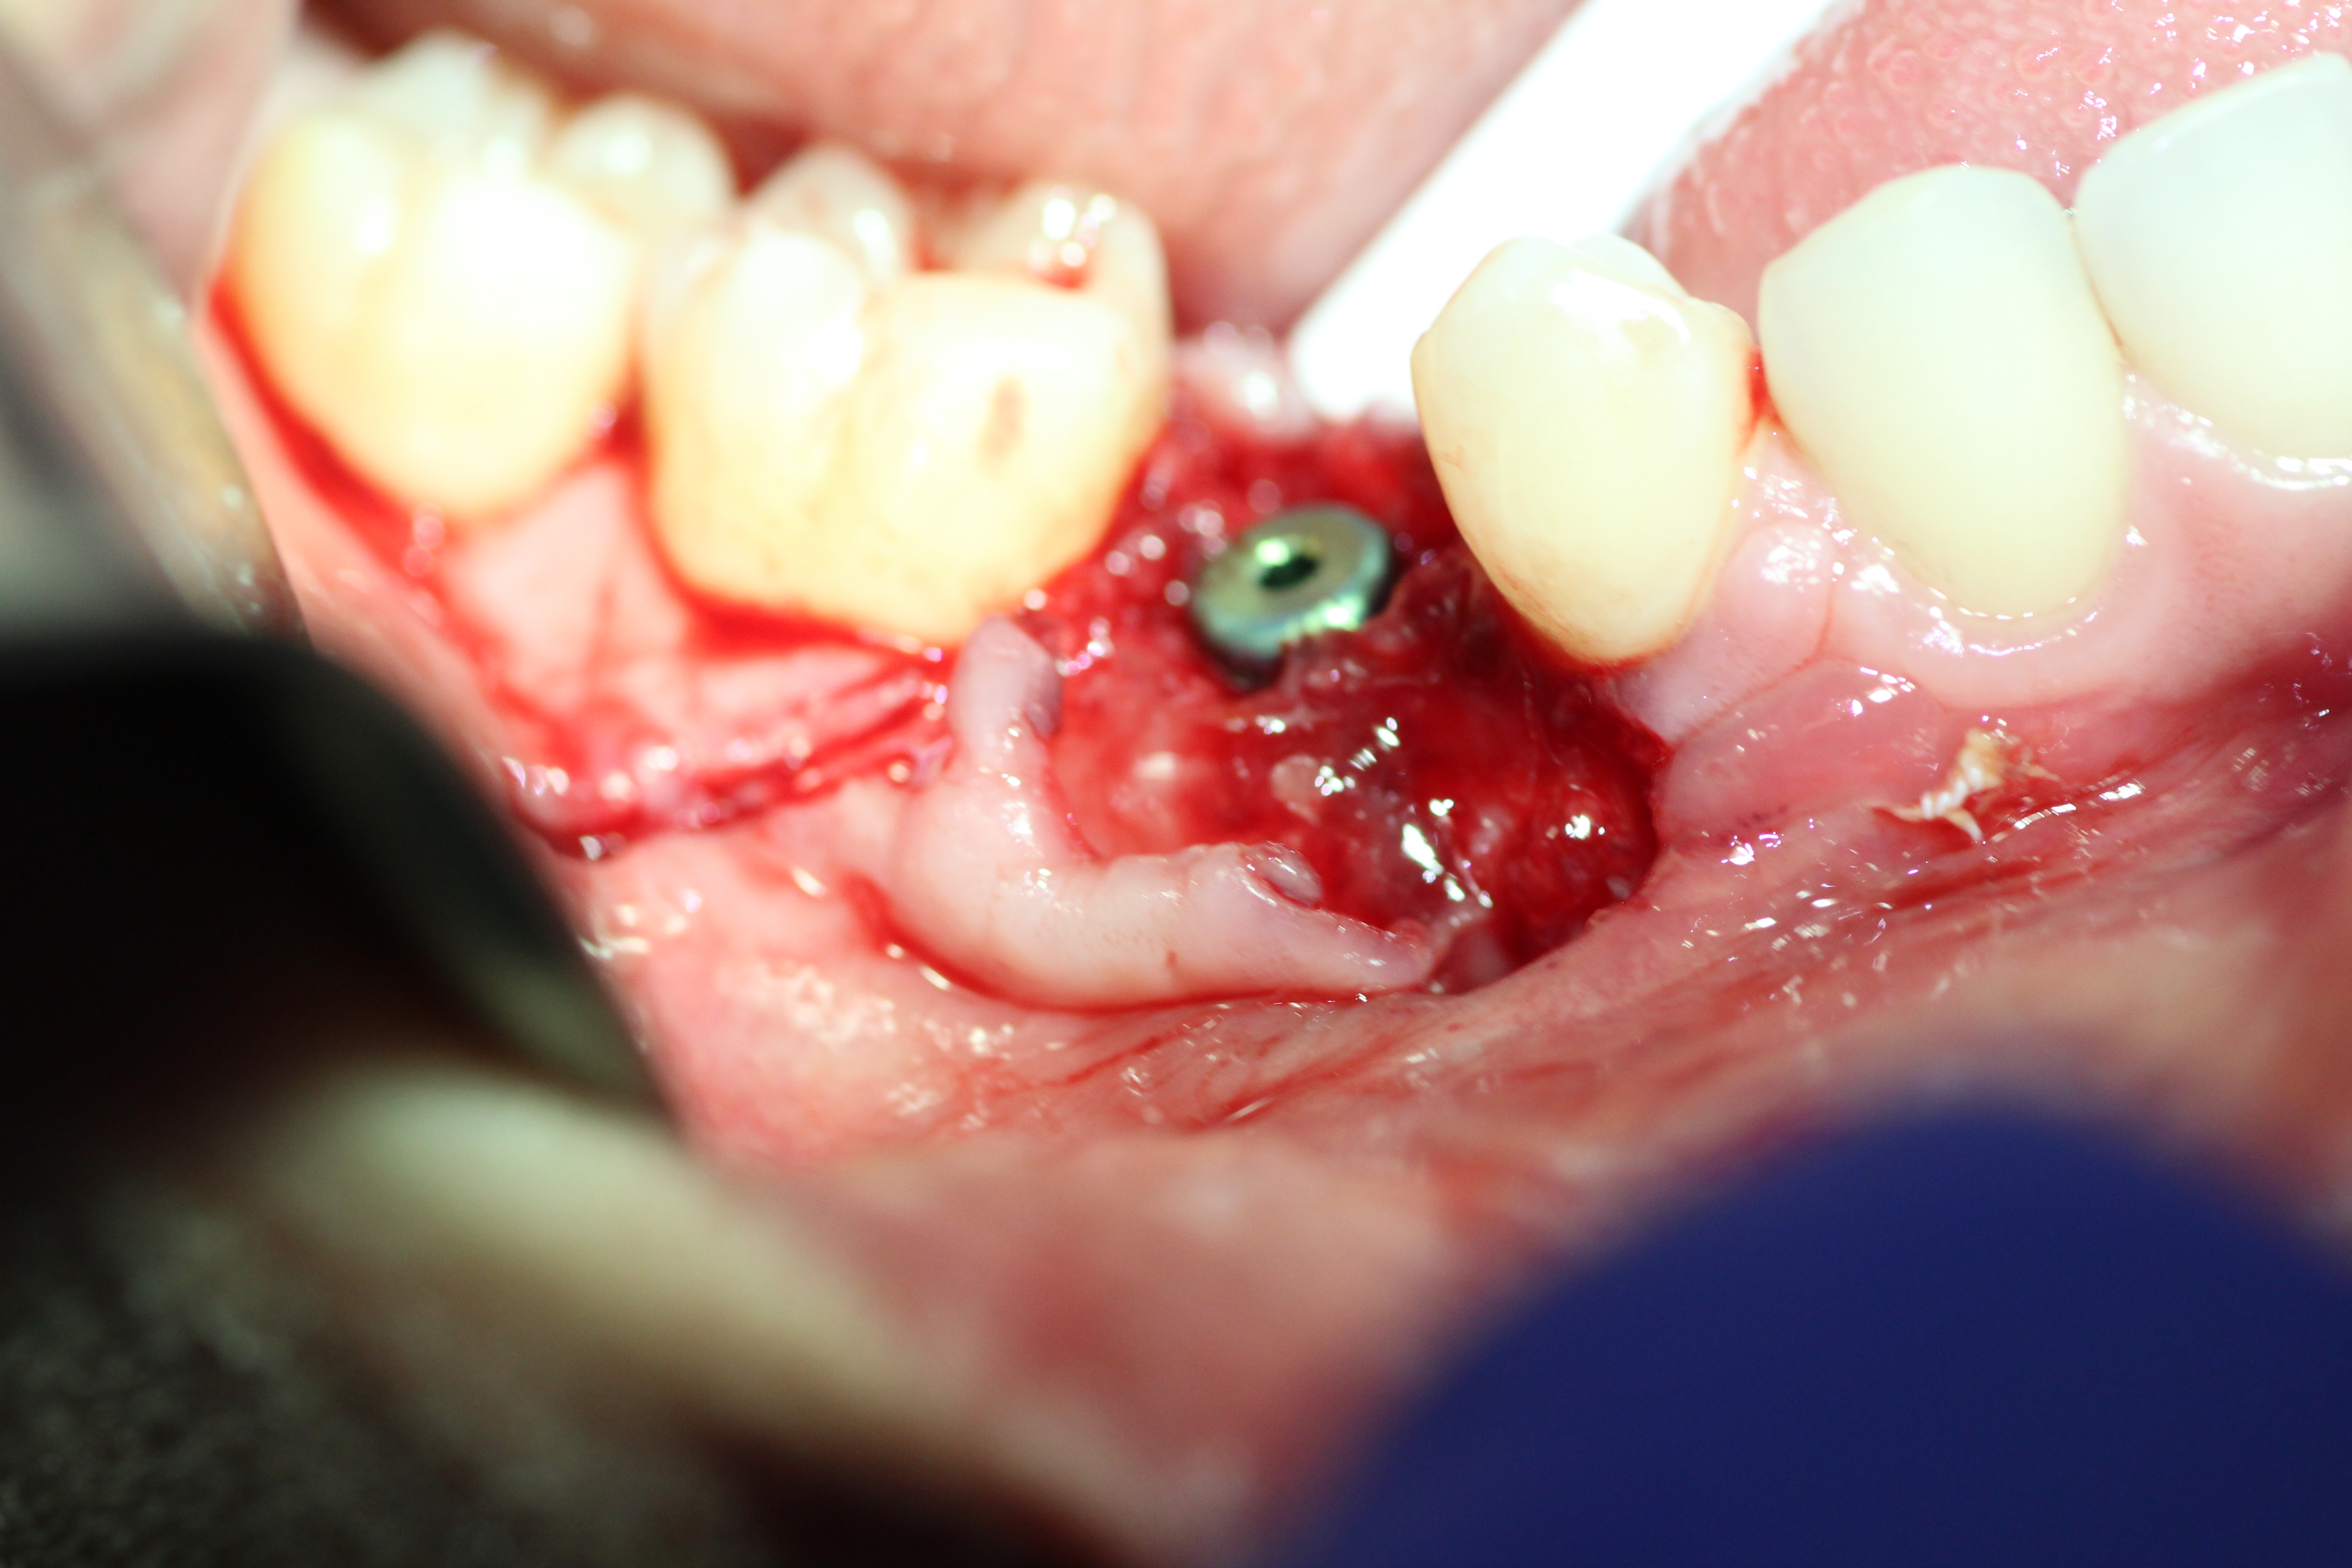

Immediate placement with bone guided regeneration.

- Implant in place with mental nerve isolated.

- 2nd stage surgery, membrane removed. Shows nice bulk of buccal bone.